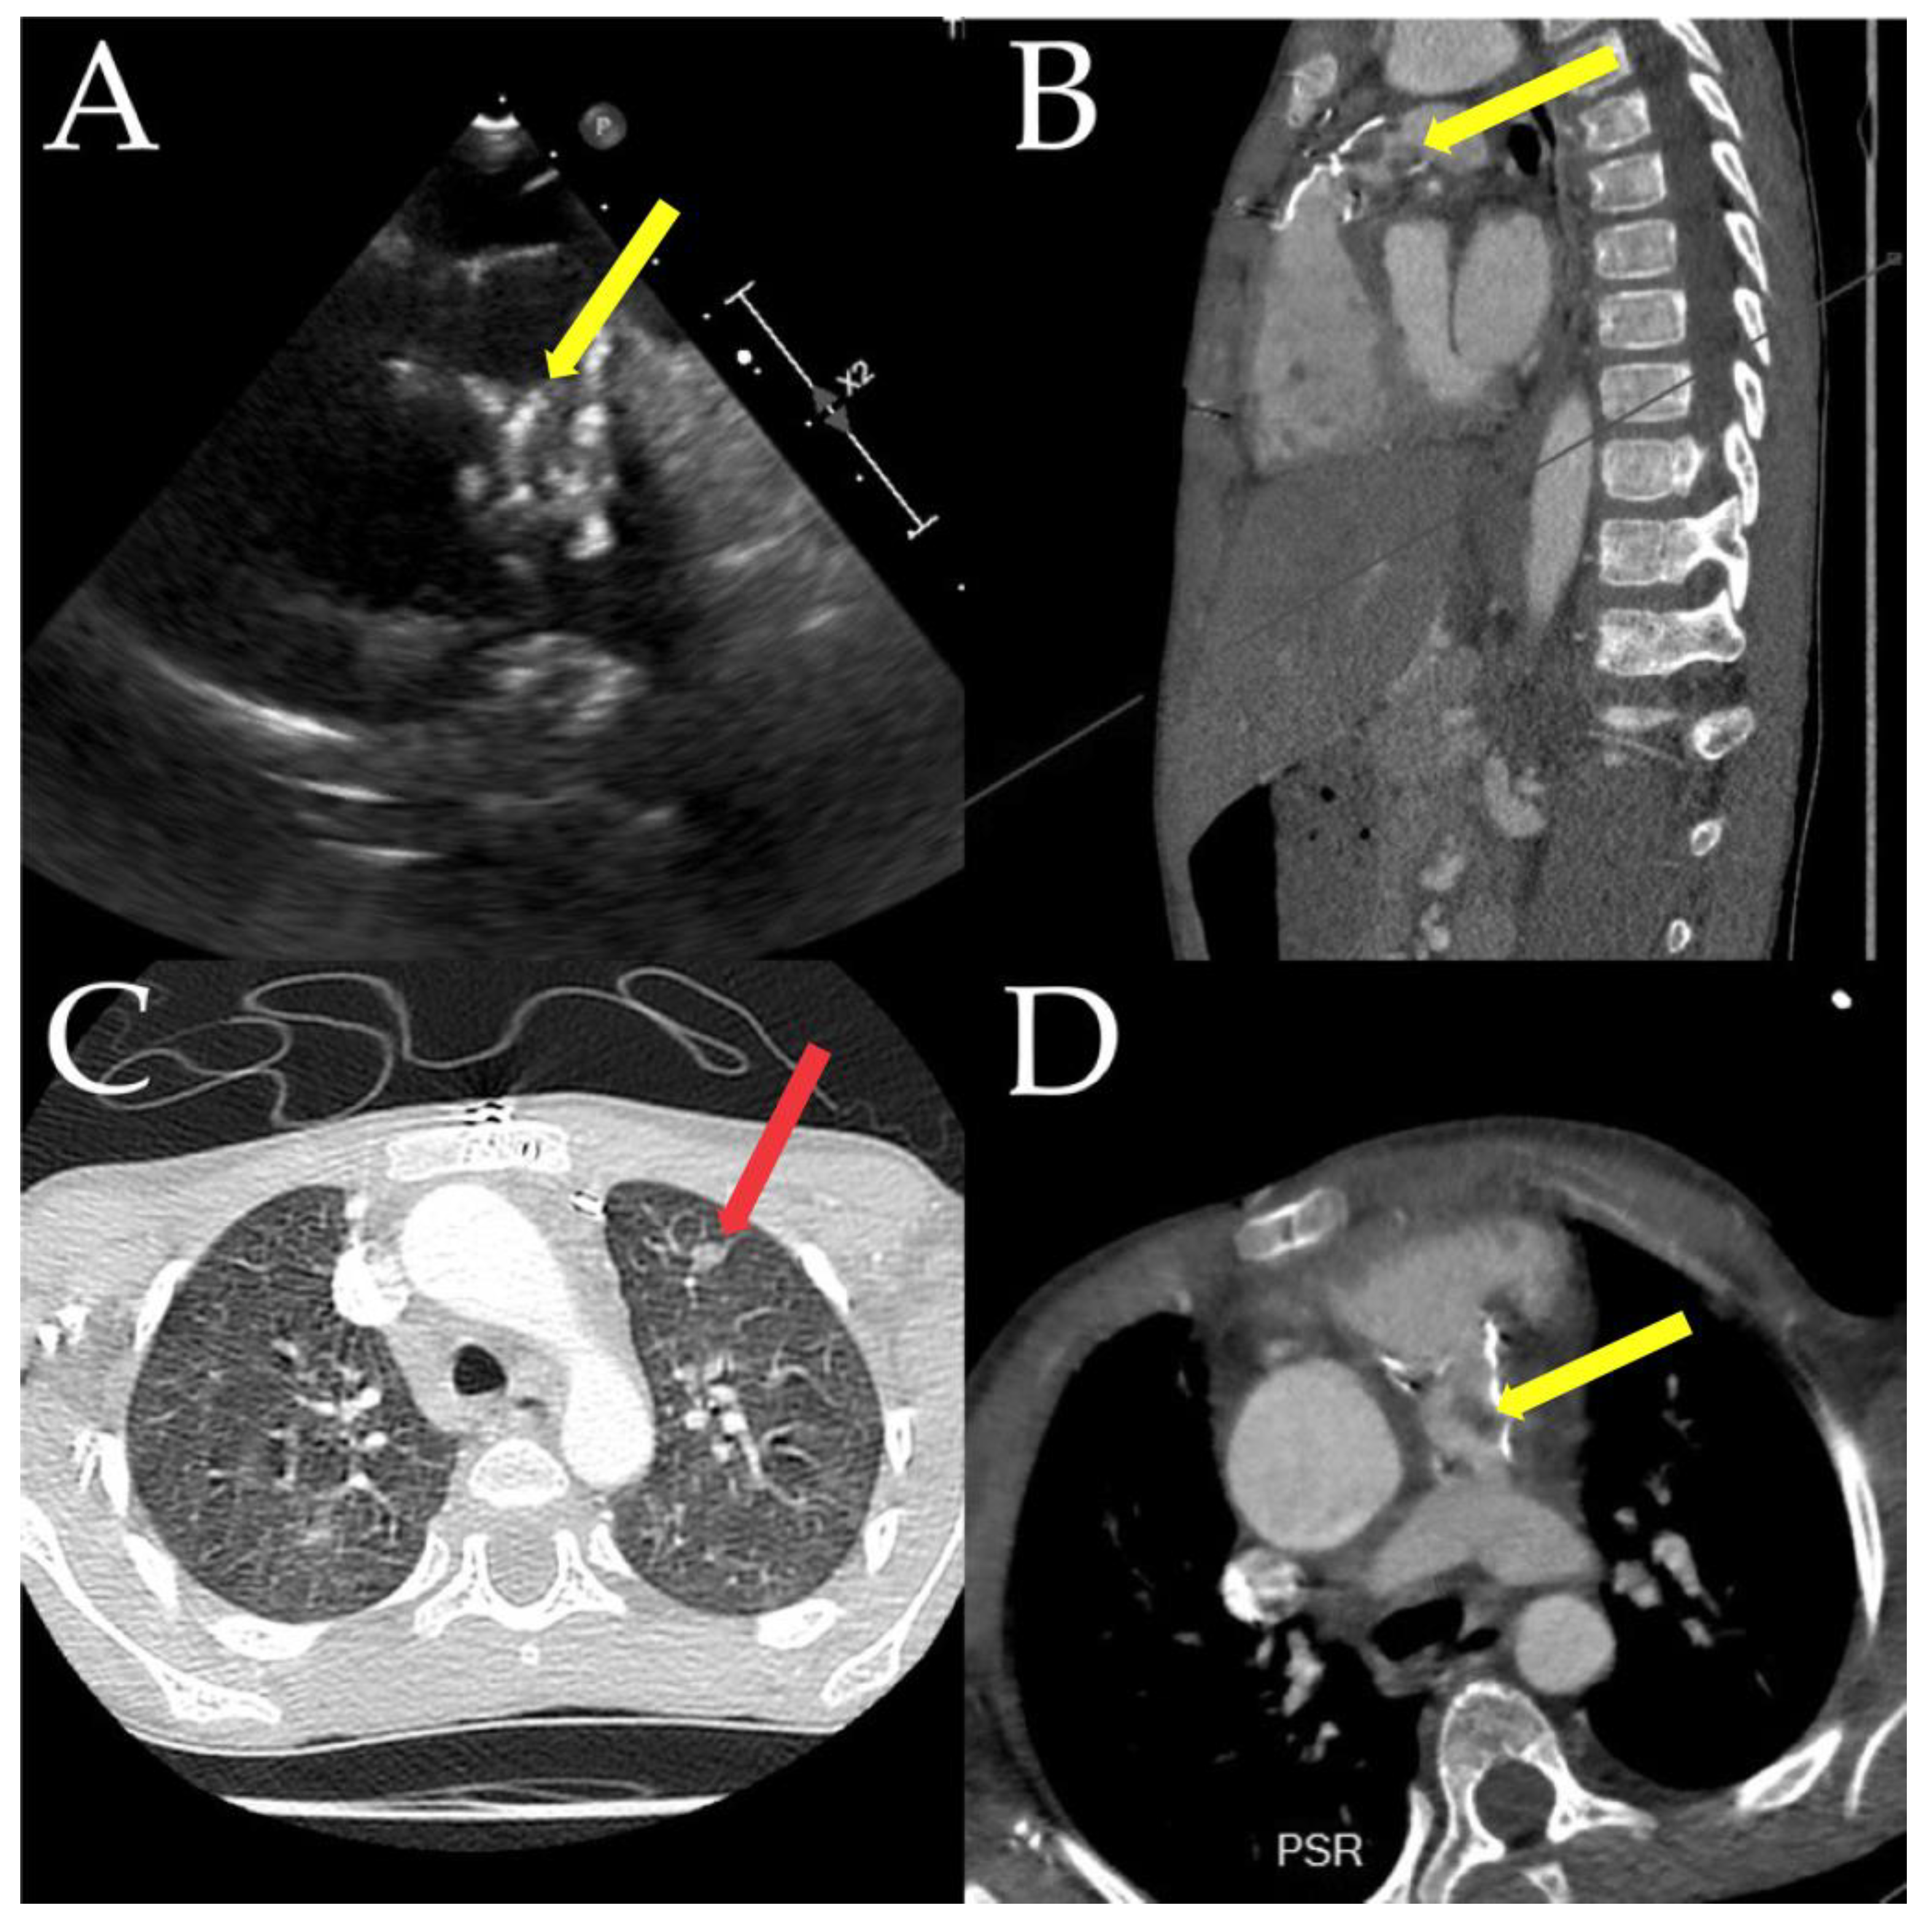

- Chau, A.; Renella, P.; Arrieta, A. Multimodality Cardiovascular Imaging in the Diagnosis and Management of Prosthetic Valve Infective Endocarditis in Children Report of Two Cases and Brief Review of the Literature. Cardiol. Young 2019, 29, 1526–1529. [Google Scholar]

- Parlow, S.; Beamish, P.; Desjardins, I.; Fulop, J.; Maharajh, G.; Castellucci, L. Infected Rastelli Conduit in an Immunocompromised Patient That Was Not Visible on Transthoracic Echocardiogram. CJC Open 2019, 1, 324–326. [Google Scholar] [PubMed]

- Parbhoo, P.; Nell, T.; Meel, R. Assessment of pacemaker lead-related infective endocarditis with three-dimensional echocardiography and cardiac computed tomography. Cardiovasc. J. Afr. 2022, 33, 36–40. [Google Scholar] [CrossRef]